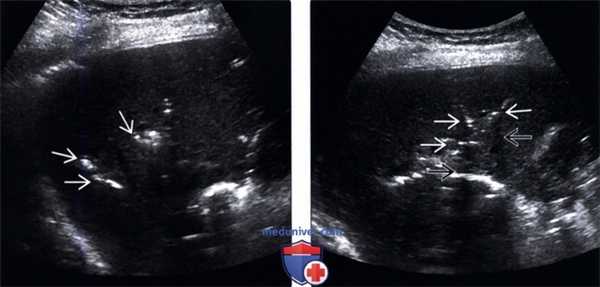

(Левый) На поперечном УЗ срезе правой доли печени определяется несколько эхогенных очагов В линейной формы, отбрасывающих «грязную» акустическую тень, что соответствует картине газа в желчных протоках.

(Правый) На поперечном УЗ срезе правой доли печени визуализируются несколько эхогенных очагов линейной формы, отбрасывающих «грязную» акустическую тень, что соответствует изменениям, возникающих при наличии газа в желчных протоках.